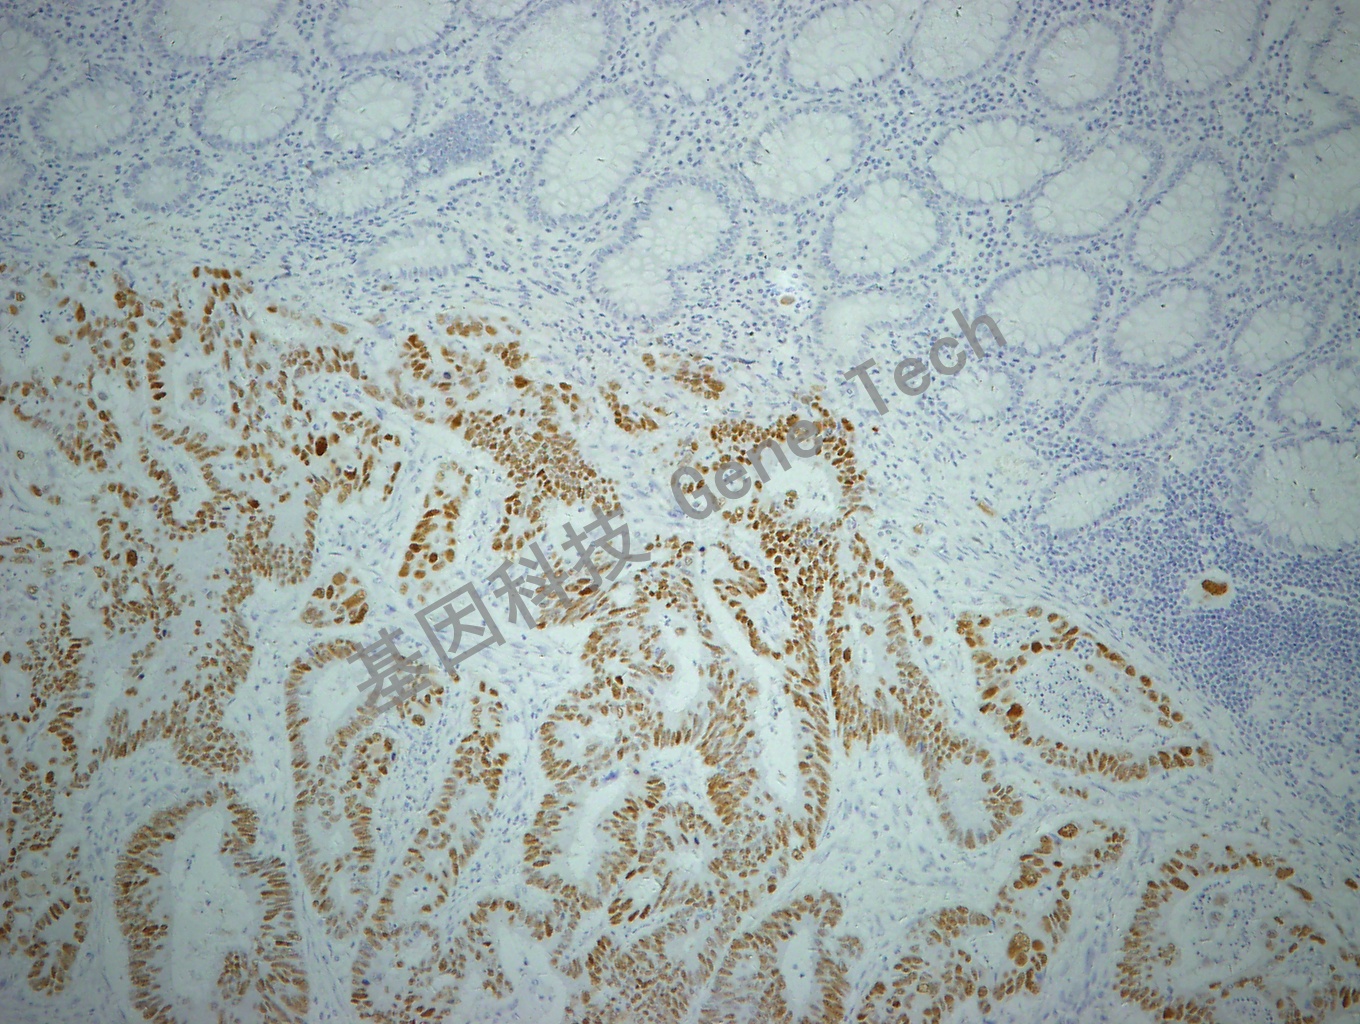

结肠癌石蜡切片,用 p53(GT2095)染色,细胞核着色,DAB 显色。

【阳性对照】结肠癌